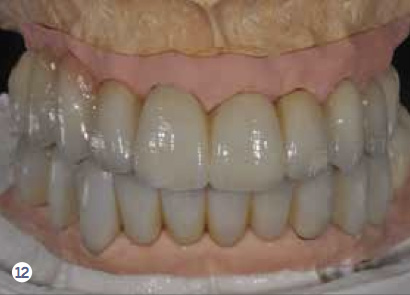

Fig 12 After all the teeth and some implants were extracted, a segmented, screw-retained, implant-supported reconstruction was fabricated and delivered.

Figure 12

Fig 13. After all the teeth and some implants were extracted, a segmented, screw-retained, implant-supported reconstruction was fabricated and delivered.

Figure 13